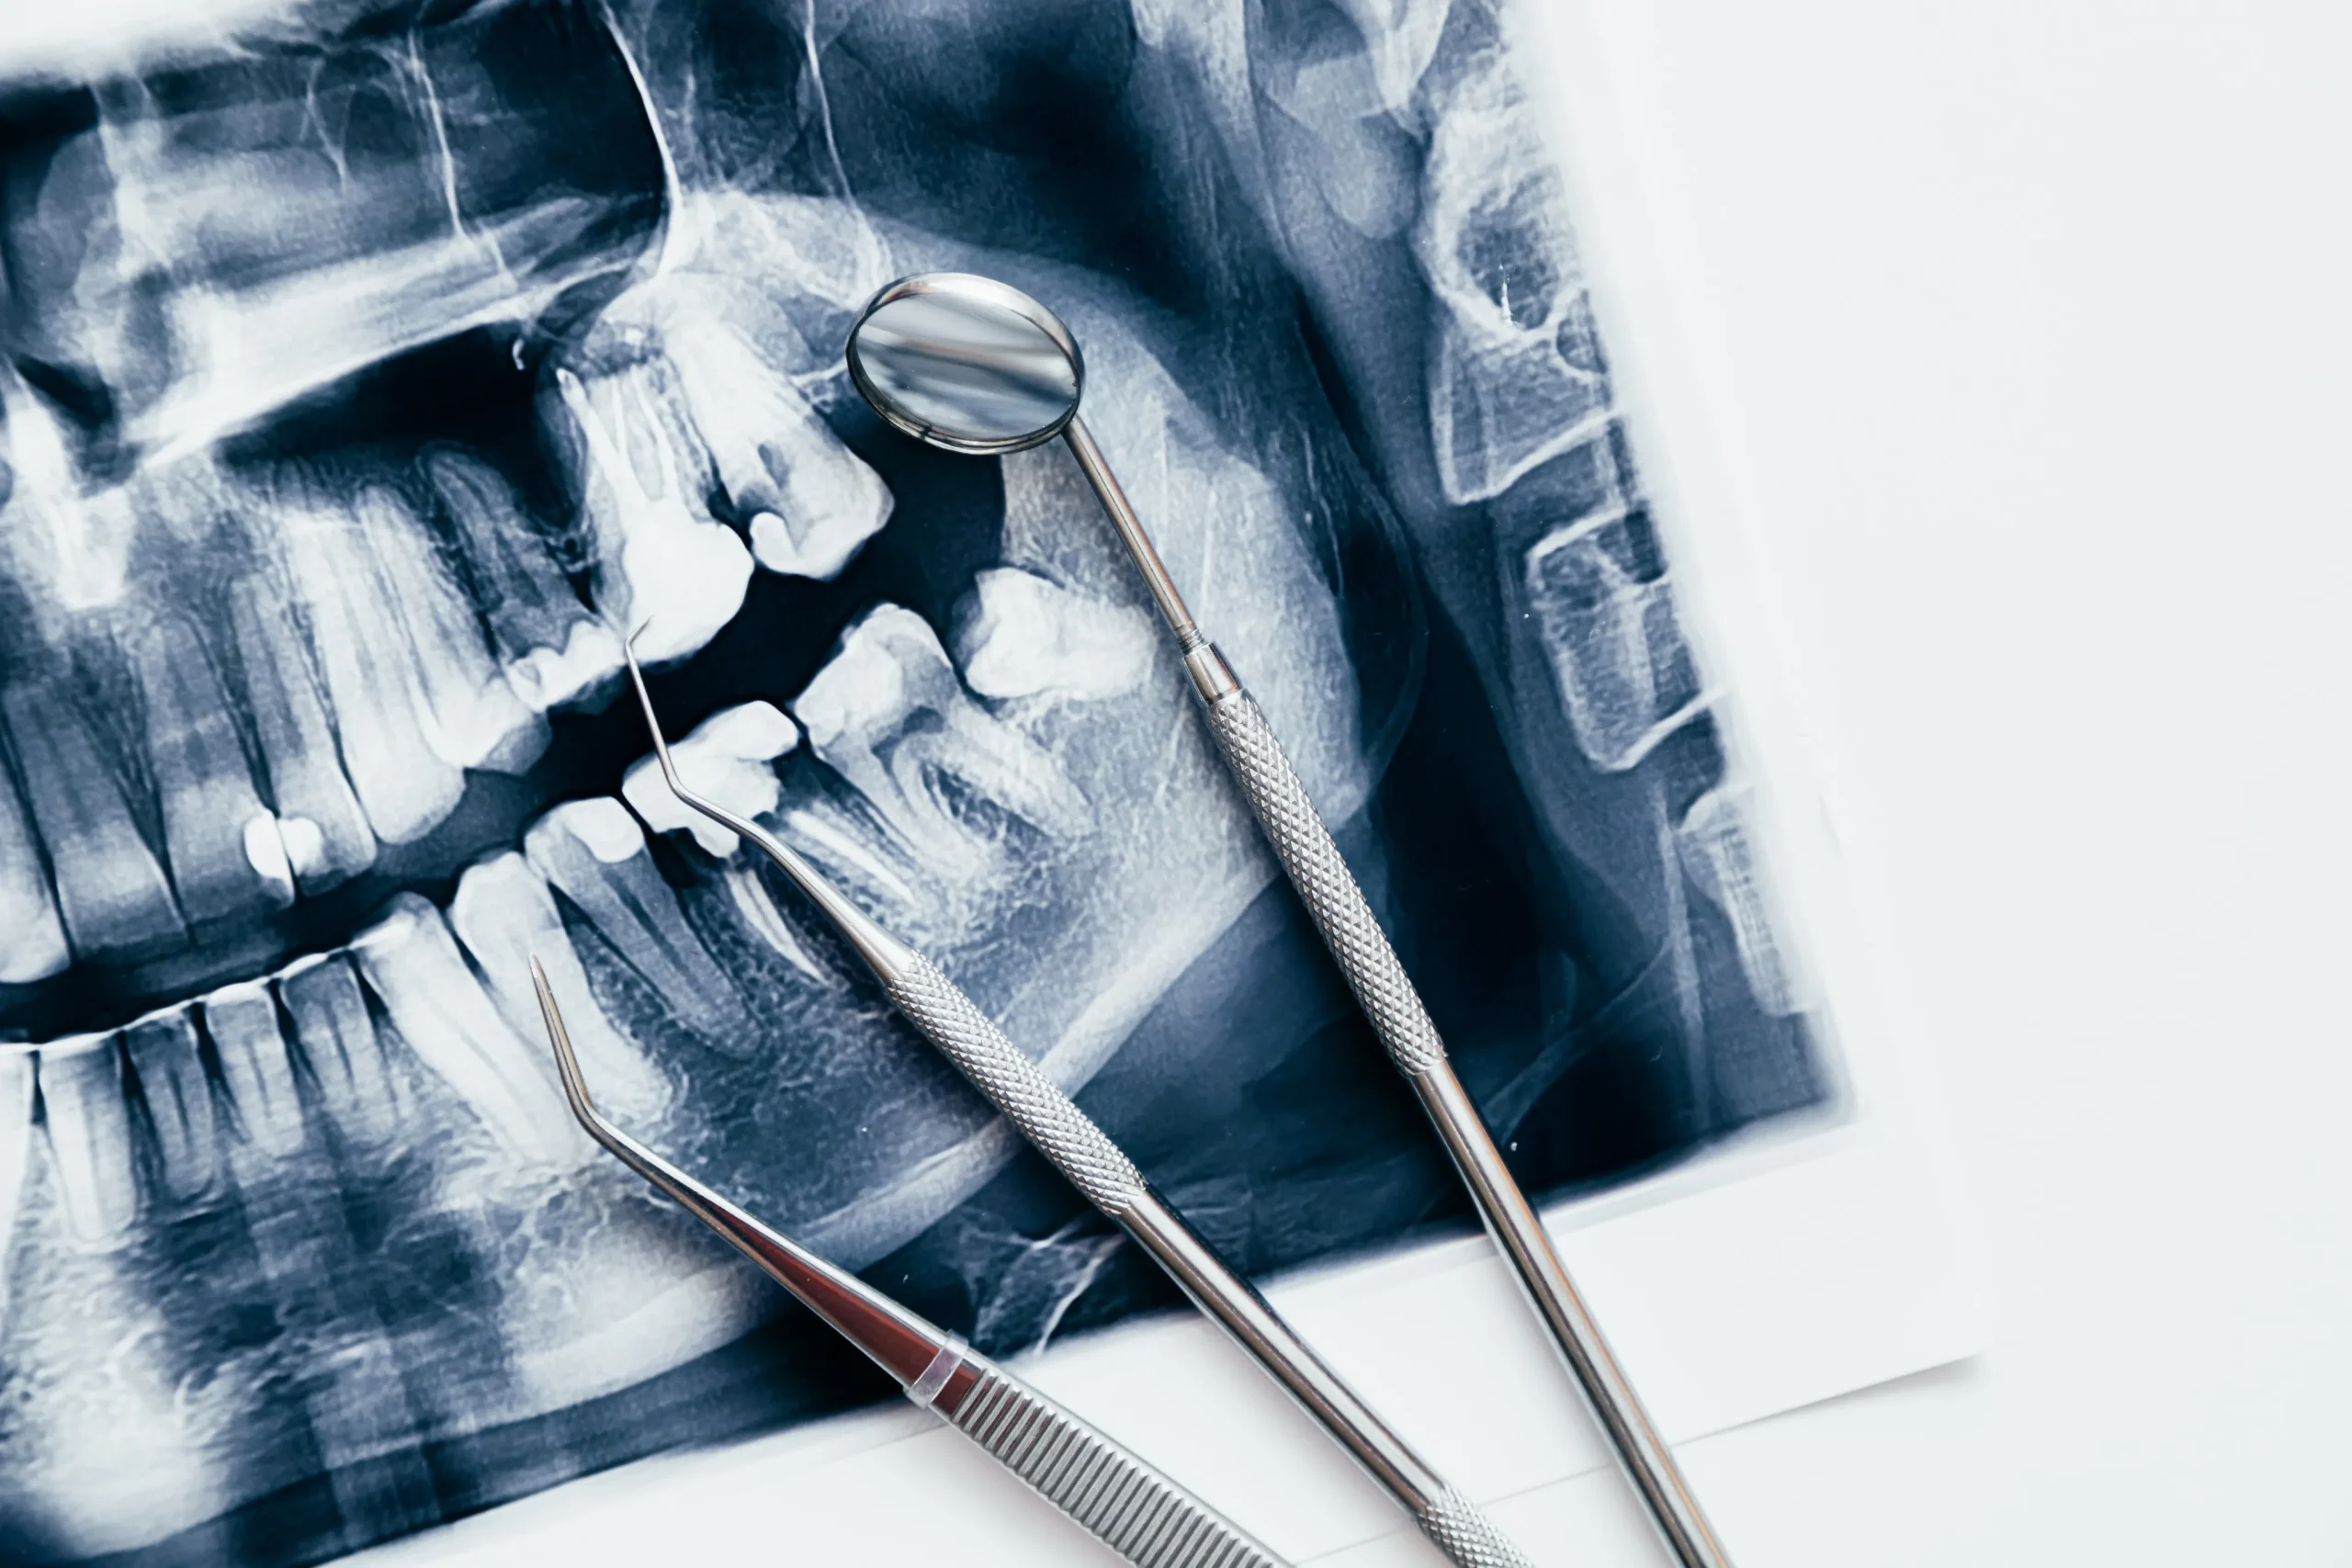

Зубы мудрости — это последние зубы, которые появляются в полости рта, обычно в возрасте 17-25 лет. Их удаление является одним из самых распространенных стоматологических вмешательств, но вопрос о том, нужно ли это делать, остается дискуссионным.

Существует множество причин, по которым стоматолог может рекомендовать удаление зубов мудрости. Они могут быть кривыми, не прорезавшимися, вызывать боль и дискомфорт, повреждать окружающие зубы и ткани. Однако, есть и другие факторы, которые могут влиять на решение об удалении или сохранении зубов мудрости.

Один из них — возраст пациента. Если зубы мудрости удалены в молодом возрасте, то процесс регенерации и заживления будет проходить быстрее, чем у старших людей. Также учитывается состояние и положение зубов мудрости, а также их влияние на соседние зубы и десны.